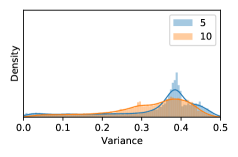

To model how different classifiers will respond to a given input , we assume that the prediction from classifier is sampled from a beta distribution that is characterized by two parameters by and . We further assume that is fixed to the same constant value for all ’s. Under this assumption, each input can be described by ( can be calculated since is fixed), easing further analysis. The Severity Level (SL) of the case represented by image can be characterized by the parameter . The larger the value of , the more severe the case of is. When and are close, the case is ambiguous as the distribution shifts towards being symmetric (i.e. signifying much disagreement among classifiers) rather than being one-sided (i.e. consensus among classifiers that is negative or positive). We provide a set of examples in Figure 2 and also Figure S.8 in the supplementary materials showing how the beta distribution can be used to capture diverse predictions given by an ensemble learner.

In contrast, the MC-dropout method showed the worst overall performance among the three, as it can be seen from the high ratios of SL0 examples among the uncertain negatives in Figure 4. The histograms in Figure 2 provides another perspective to look into the phenomenon, where a decent proportion of MC-dropout model’s predictions on SL0 inputs entailed low confidence (far from 0 or 1), which from another angle explained why MC-dropout was less specific in terms of lower FNP; many no-DR inputs (i.e. SL0) were erroneously assigned high uncertainty by MC-dropout models.